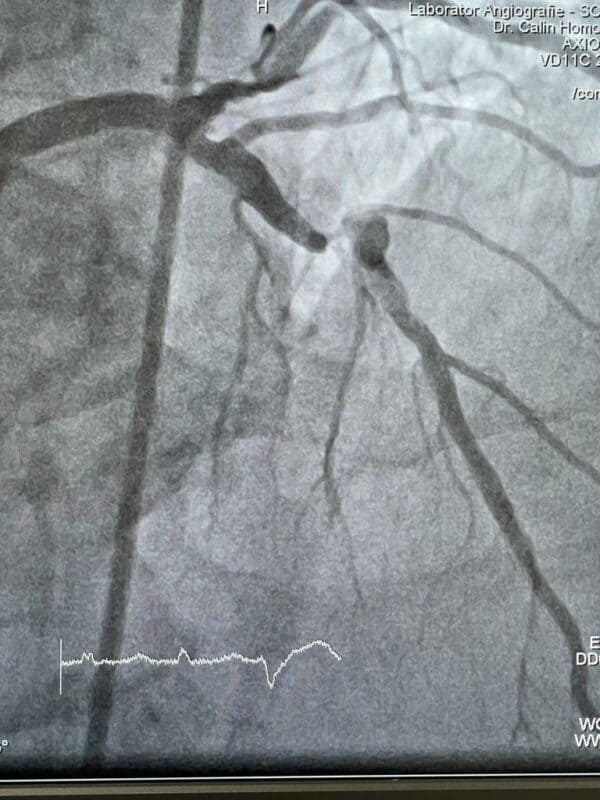

Tehnica de rotablație coronariană a fost folosită cu succes pentru prima oară la Spitalul Clinic Județean de Urgență Cluj-Napoca.

„Trei pacienți au beneficiat, cu succes, de un tratament intervențional utilizat pentru prima oară în spital. Este vorba de tehnica de rotablație coronariană, care a permis tratamentul unor leziuni calcifice complexe, de care sufereau cei trei pacienți. Din cauza durității acestor leziuni, ele nu pot fi tratate prin tehnici convenționale de dilatare şi stentare.

Astfel, în cazul rotablației, cateterul este o „mini-freză”, cu un vârf de diamant, care poate ajunge la 160.000 rotații/ minut, sub acțiunea aerului comprimat. Dispozitivul este introdus percutan în lumenul coronarian și, prin frezarea leziunilor calcifice, se pregătește implantarea stentului.

Înainte

După intervenție

Intervenția în premieră a fost realizată de o echipă de medici experimentați, din cadrul Secției Cardiologie II (Cardiologie intervențională), condusă de Conf. Dr. Dan Olinic, medicul șef al secției, cu participarea Dr. Călin Homorodean, Dr. Mihai Ober, Dr. Dan Tătaru şi Dr. Mihail Spînu. Din partea Institutului de Cardiologie CC. Iliescu din Bucureşti, a fost invitat Dr. Marin Postu, ca specialist experimentat în utilizarea rotablaţiei.